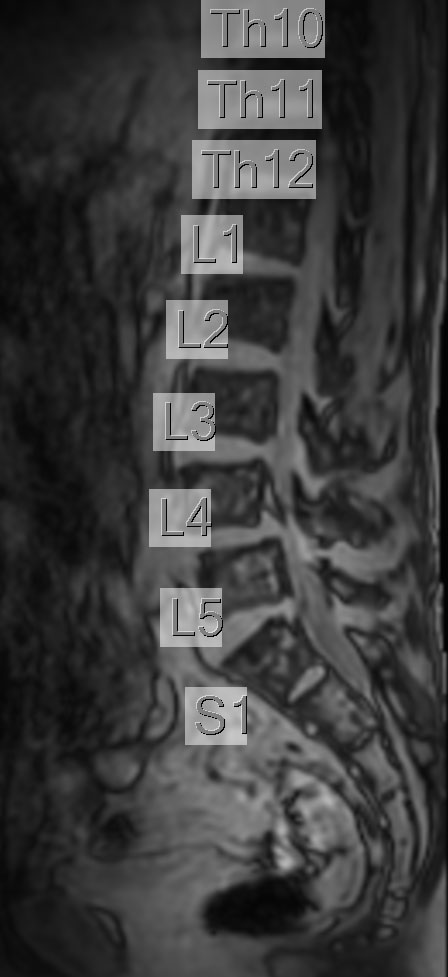

Lumbar Spine disc herniation

Patient with a lumbar spine disc herniation.